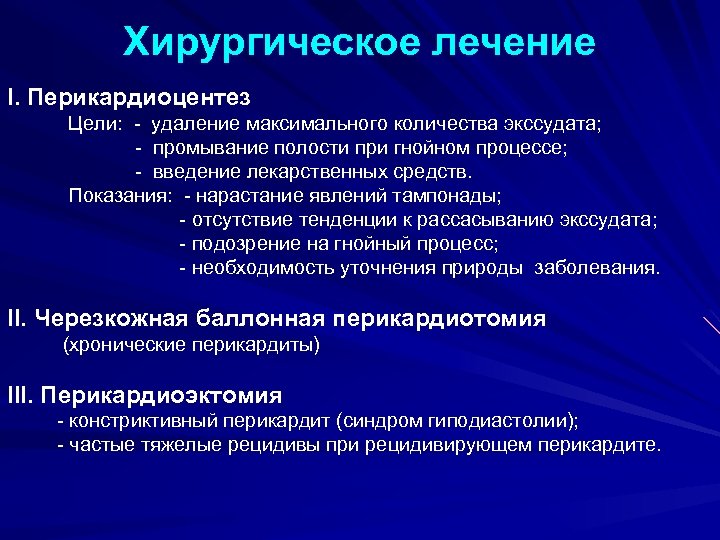

Хирургическое лечение I. Перикардиоцентез Цели: - удаление максимального количества экссудата; - промывание полости при гнойном процессе; - введение лекарственных средств. Показания: - нарастание явлений тампонады; - отсутствие тенденции к рассасыванию экссудата; - подозрение на гнойный процесс; - необходимость уточнения природы заболевания. II. Черезкожная баллонная перикардиотомия (хронические перикардиты) III. Перикардиоэктомия - констриктивный перикардит (синдром гиподиастолии); - частые тяжелые рецидивы при рецидивирующем перикардите.